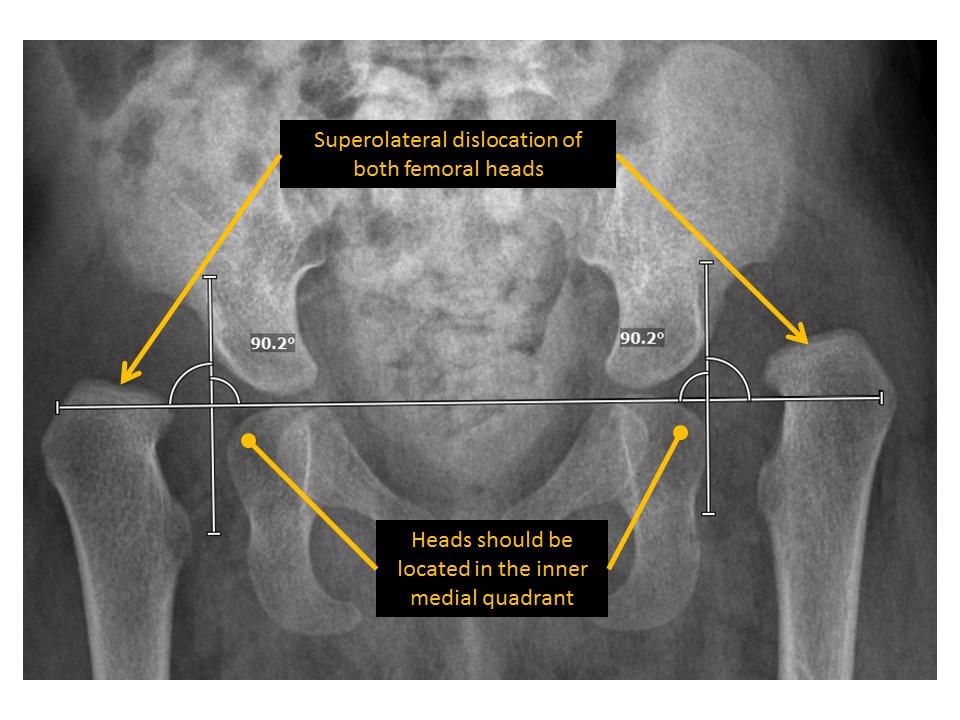

There is hip dislocation or subluxation. [Yes/No]

The center edge angle of the femoral heads is abnormal. [Yes/No]